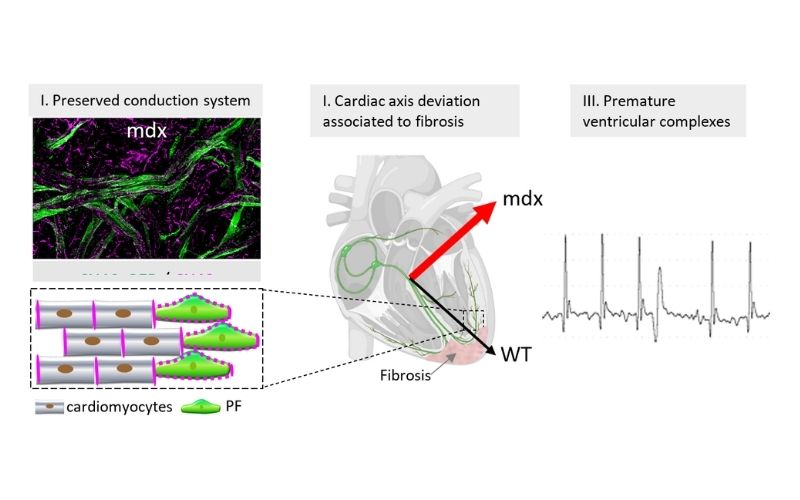

Cardiac defects in a mouse model of Duchenne dystrophy (Mdx)

New study challenges the link between Purkinje fibers and heart arrhythmias in Duchenne muscular dystrophy.

Cardiac regeneration is not as perfect as it has been claimed

Cardiac regeneration leads to hyperplastic Purkinje fiber network in association with ventricular conduction disorders.